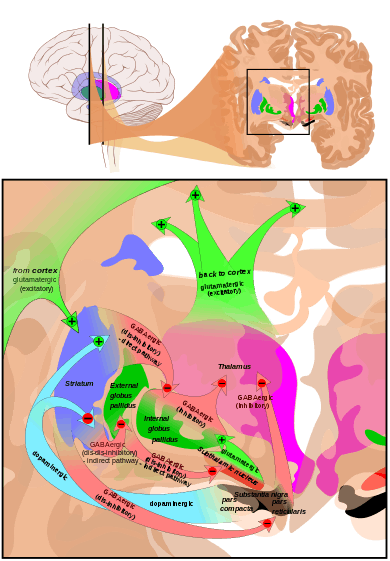

The most important afferent in terms of quantity of axons is the corticostriatal connection. Many parts of the neocortex innervate the dorsal striatum. The cortical pyramidal neurons projecting to the striatum are located in layers II-VI, but the most dense projections come from layer V.[18] They end mainly on the spines of the spiny neurons. They are glutamatergic, exciting striatal neurons. Another well-known afferent is the nigrostriatal connection arising from the neurons of the substantia nigra pars compacta. While cortical axons synapse mainly on spine heads of spiny neurons, nigral axons synapse mainly on spine shafts. In primates, the thalamostriatal afferent comes from the central median-parafascicular complex of the thalamus (see primate basal ganglia system). This afferent is glutamatergic. The participation of truly intralaminar neurons is much more limited. The striatum also receives afferents from other elements of the basal ganglia such as the subthalamic nucleus (glutamatergic) or the external globus pallidus (GABAergic).

Targets (efferent connections)

Striatal outputs from both the dorsal and ventral components are primarily composed of medium spiny neurons (MSNs), a type of projection neuron, which have two primary phenotypes: "indirect" MSNs that express D2-type receptors and "direct" MSNs that express D1-type receptors.[2][4]

The basal ganglia core is made up of the striatum along with the regions to which it projects directly, via the striato-pallidonigral bundle. The striato-pallidonigral bundle is a very dense bundle of sparsely myelinated axons, giving a whitish appearance. This projection comprises successively the external globus pallidus (GPe), the internal globus pallidus (GPi), the pars compacta of the substantia nigra (SNc), and the pars reticulata of substantia nigra (SNr). The neurons of this projection are inhibited by GABAergic synapses from the dorsal striatum. Among these targets, the GPe does not send axons outside the system. Others send axons to the superior colliculus. Two others comprise the output to the thalamus, forming two separate channels: one through the internal segment of the globus pallidus to the ventral oralis nuclei of the thalamus and from there to the cortical supplementary motor area (SMA) and another through the substantia nigra to the ventral anterior nuclei of the thalamus and from there to the frontal cortex and the oculomotor cortex.